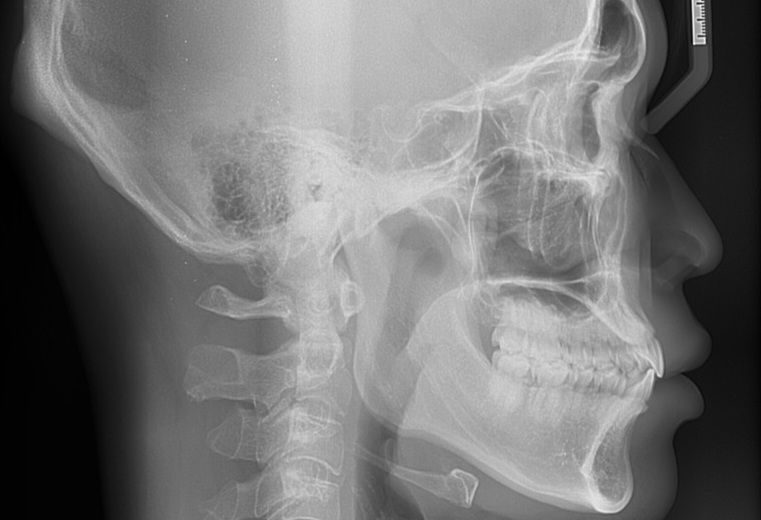

현재 치아각도나 치축의 각도가 정상범위에 있는지 알고 싶어서 질문 작성했습니다

보이는 부분에 있어서는 정상각도에서 크게 벗어나지는 않으나 이는 전방위적인 평가 및 골격과 함께 평가를 해보아야 합니다. 지금 상태로 보았을 때는 교정을 해서 치축을 돌려야할 만큼의 문제는 아니며 일반 사람들이라면 평생 교정을 하지 않고 살아가는 분들도 많습니다.

단순 임상사진과 cephalo만 봐서는 정확히는 알 수 없으나 교정치과에서 제대로 한 치료라면 문제 없을 것으로 사료됩니다.